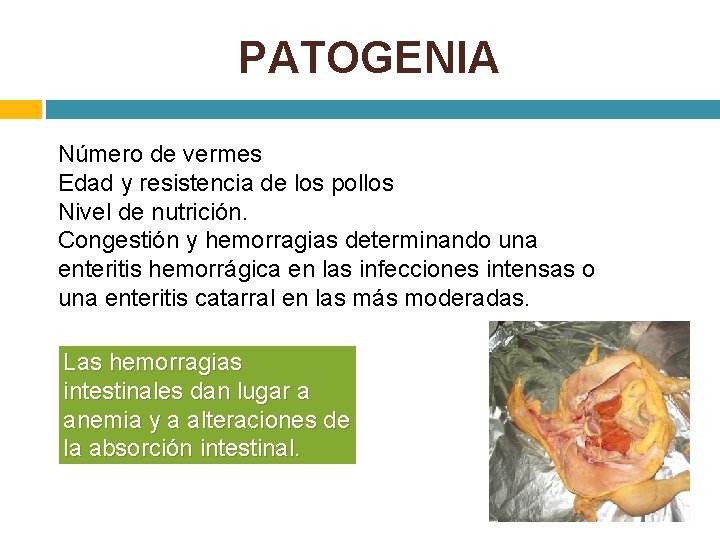

PATOGENIA Número de vermes Edad y resistencia de los pollos Nivel de nutrición. Congestión y hemorragias determinando una enteritis hemorrágica en las infecciones intensas o una enteritis catarral en las más moderadas. Las hemorragias intestinales dan lugar a anemia y a alteraciones de la absorción intestinal.

SINTOMATOLOGIA El crecimiento de los pollos se detiene, dejan de comer, están adormecidos y con las plumas erizadas y se observan excrementos diarreicos, frecuentemente sanguinolentos